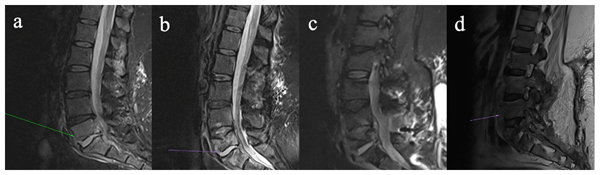

Diagnostic value of magnetic resonance imaging and the outcomes of medical therapy in histologically confirmed diabetes-related foot osteomyelitis

Abhay Mishra, Paige Lyell, and David M. Bamberger

J. Bone Joint Infect., 10, 411–417, https://doi.org/10.5194/jbji-10-411-2025,https://doi.org/10.5194/jbji-10-411-2025, 2025

Short summary